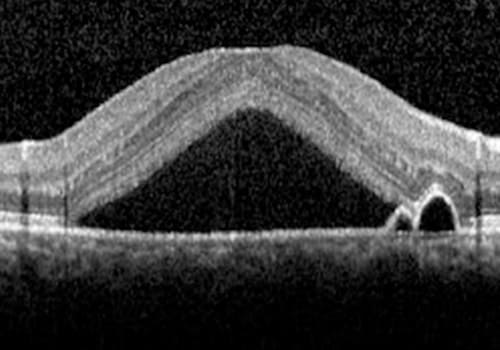

Como é realizado do diagnóstico?

Com exames realizados por oftalmologista especialista em retina, incluindo:

•Tomografia de coerência óptica (OCT)